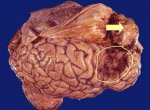

Самая большая проблема, которая может произойти с нашим мозгом это опухоль. Ее очень сложно извлечь из головы больного, а Вылечить так вообще нереально. Проблема в наши дни стала очень распространенной в больницы все чаще и чаще обращаются люди с очень сильной головной болью и другими симптомами опухоли. Вот только если в начальной стадии болезнь вылечить еще можно, то вот во второй и дальше